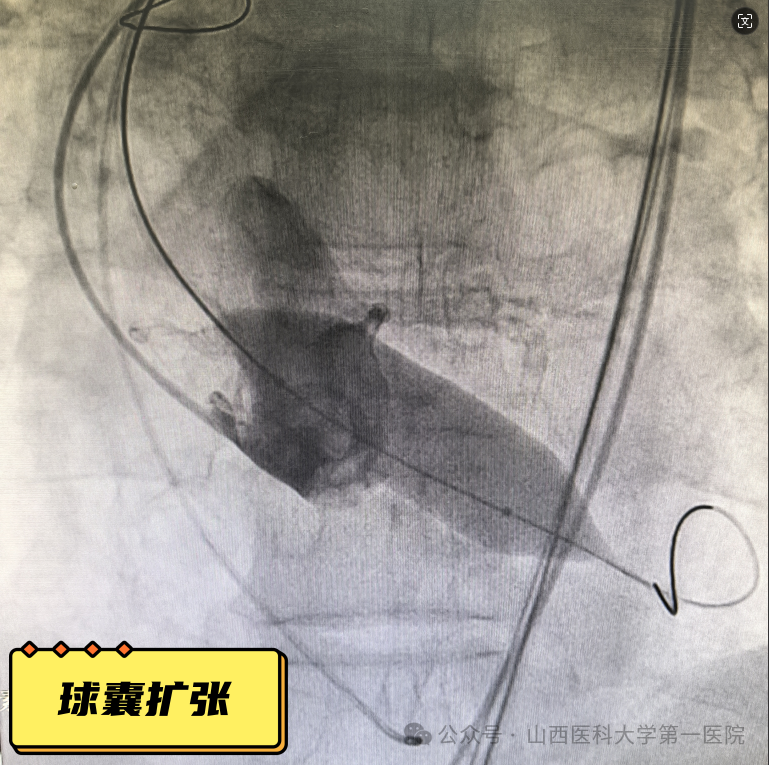

70岁的王大爷近三年来反复出现活动后心慌、气短,1个月前症状明显加重,出现1次晕厥,当地医院诊断为:主动脉瓣重度狭窄,建议手术治疗,为求进一步诊治来到山医大一院心脏大血管外科。患者既往有心梗病史,2016年曾于前降支植入一枚支架,郭建军主任医师、曹森垚副主任医师接诊后高度重视患者,入院后完善心脏彩超及化验指标提示:主动脉瓣重度狭窄,心功能不全,射血分数34%,NT-proBNP 3494pg/ml,积极调整心功能,同时综合考虑病情及年龄认为经导管主动脉瓣置换术(TAVR)是最佳手术方式,随后进一步完善TAVR术前检查,静息心肌灌注断层显像示:左室壁心尖段、前壁中间段和基底段薄弱,LVEF:30%,颈-胸CTA提示:主动脉瓣二叶畸形,重度钙化,心脏角度约66°。

经积极治疗及系统检查后,患者病情仍不容乐观,心功能极差,经反复抗心衰治疗效果不佳,围术期心功能衰竭风险高;主动脉瓣狭窄严重,瓣口面积小,瓣周钙化严重,钙化积分高,导丝跨瓣难度大,球囊扩张后斑块脱落致体循环栓塞风险高;横位心导致手术难度大、瓣架移位风险高;左室壁薄弱,术中出现心脏穿孔风险高;单纯主动脉瓣狭窄,术中循环崩溃可能大。郭建军主任医师团队格外慎重,为保证手术顺利进行多次组织心血管内科、神经内科、麻醉科、手术供应室、超声影像科及CT放射影像科等多学科会诊,经反复研究,针对术中可能出现的情况和并发症做了充分准备和相关预案,最终在结构性心脏病介入团队的默契配合及多学科医护人员的协助下,顺利完成TAVR手术。患者术后第二日便可下地活动,自觉症状明显好转,复查心脏彩超显示:主动脉瓣开放正常,跨瓣流速及压差正常,未见反流,心功能明显好转,LVEF54%。